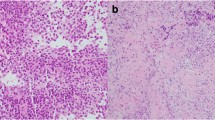

Among patients in the Severance Hospital Pituitary Tumor Cohort, 232 subjects received transsphenoidal adenomectomy following a diagnosis of GH-secreting pituitary adenoma from January 2012 to January 2017 at Severance Hospital, Yonsei University College of Medicine, Seoul, Korea. All the enrolled patients were single ethnicity, Korean. GH-secreting pituitary tumors were confirmed by measuring serum insulin-like growth factor-1 (IGF-1) and nadir GH levels during the 75-g oral glucose tolerance test. Immunohistochemical staining of the operated pituitary tumors was performed for GH, prolactin, luteinizing hormone, follicle-stimulating hormone, thyroid stimulating hormone, and adrenocorticotropic hormone. Pituitary tumors expressing hormones other than GH were excluded from this study. Finally, the tumor tissues of 140 patients with acromegaly expressing only GH were evaluated. No patients had a family history of pituitary adenoma. Pituitary tumors were classified based on dynamic magnetic resonance imaging of the sella turcica and parasellar region according to the modified Hardy radiological classifications, as described previously35.